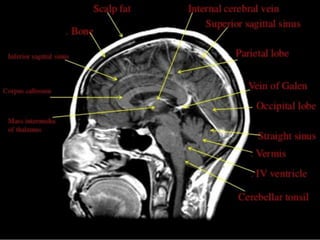

The two occipital lobes

• Are the smallest of four paired lobes in the

human cerebral cortex.

• Separated from parietal lobe by: Parieto-occipital

sulcus.